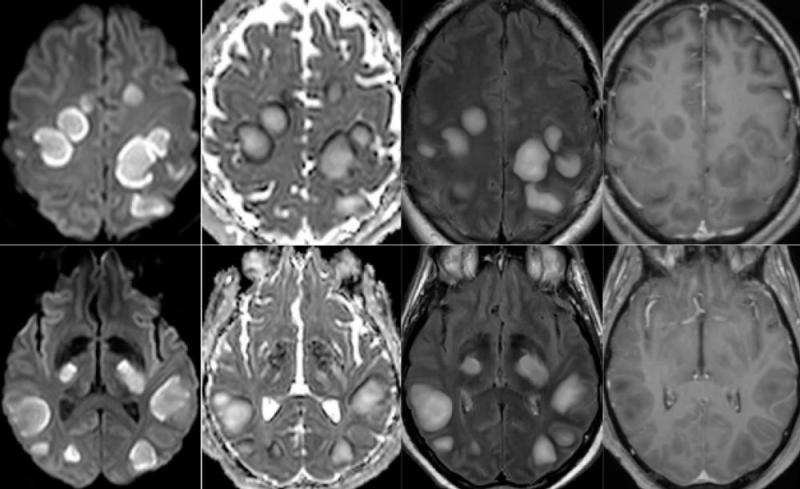

Among the 37 patients included, 28/37 (76%) were associated with one neuroimaging pattern, 7/37 (19%) with two patterns, and 2/37 (5%) showed three patterns. The most frequent MRI findings were: signal abnormalities located in the medial temporal lobe in 16/37 (43%) patients, non-confluent multifocal white matter hyperintense lesions on FLAIR and diffusion sequences, with variable enhancement, with associated hemorrhagic lesions in 11/37 patients (30%), and extensive and isolated white matter microhemorrhages in 9/37 patients (24%).